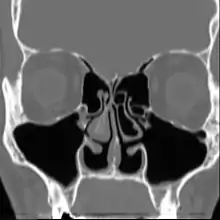

Altered nasal anatomy after bilateral subtotal inferior turbinectomy, the removal of most turbinate tissue. | |